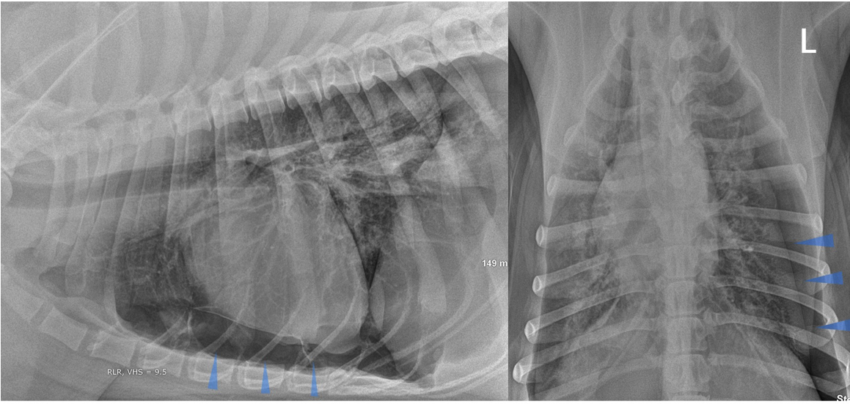

- Рентгенография. При патологиях ОГК обязательно делают обзорный снимок, опционально – прицельный. Возможно обнаружение переломов ребер, гемо- и пневмоторакса, пневмомедиастинума. При травмах лица выполняют рентгенограммы орбиты, костей носа, скуловой кости. Иногда требуется рентгенография черепа для исключения переломов его мозговой части.

Рентгенологическое исследование обнаруживает, что подвижность диафрагмы ограничена. Фиксируют повышенную воздушность легочных полей. Купол диафрагмы расположен низко и уплощен. В легочных полях мало сосудистых теней. Усиление легочного рисунка можно обнаружить при буллезной эмфиземе. С помощью рентгенографии можно обнаруживать характерное осложнение буллезной формы эмфиземы — спонтанный пневмоторакс.

Полностью образование эмфиземы и ее размеры возможно определить только при помощи рентгенографии — только этот диагностический метод поможет понять, как сильно расширились альвеолы — дыхательные ячейки, из которых состоят легкие.